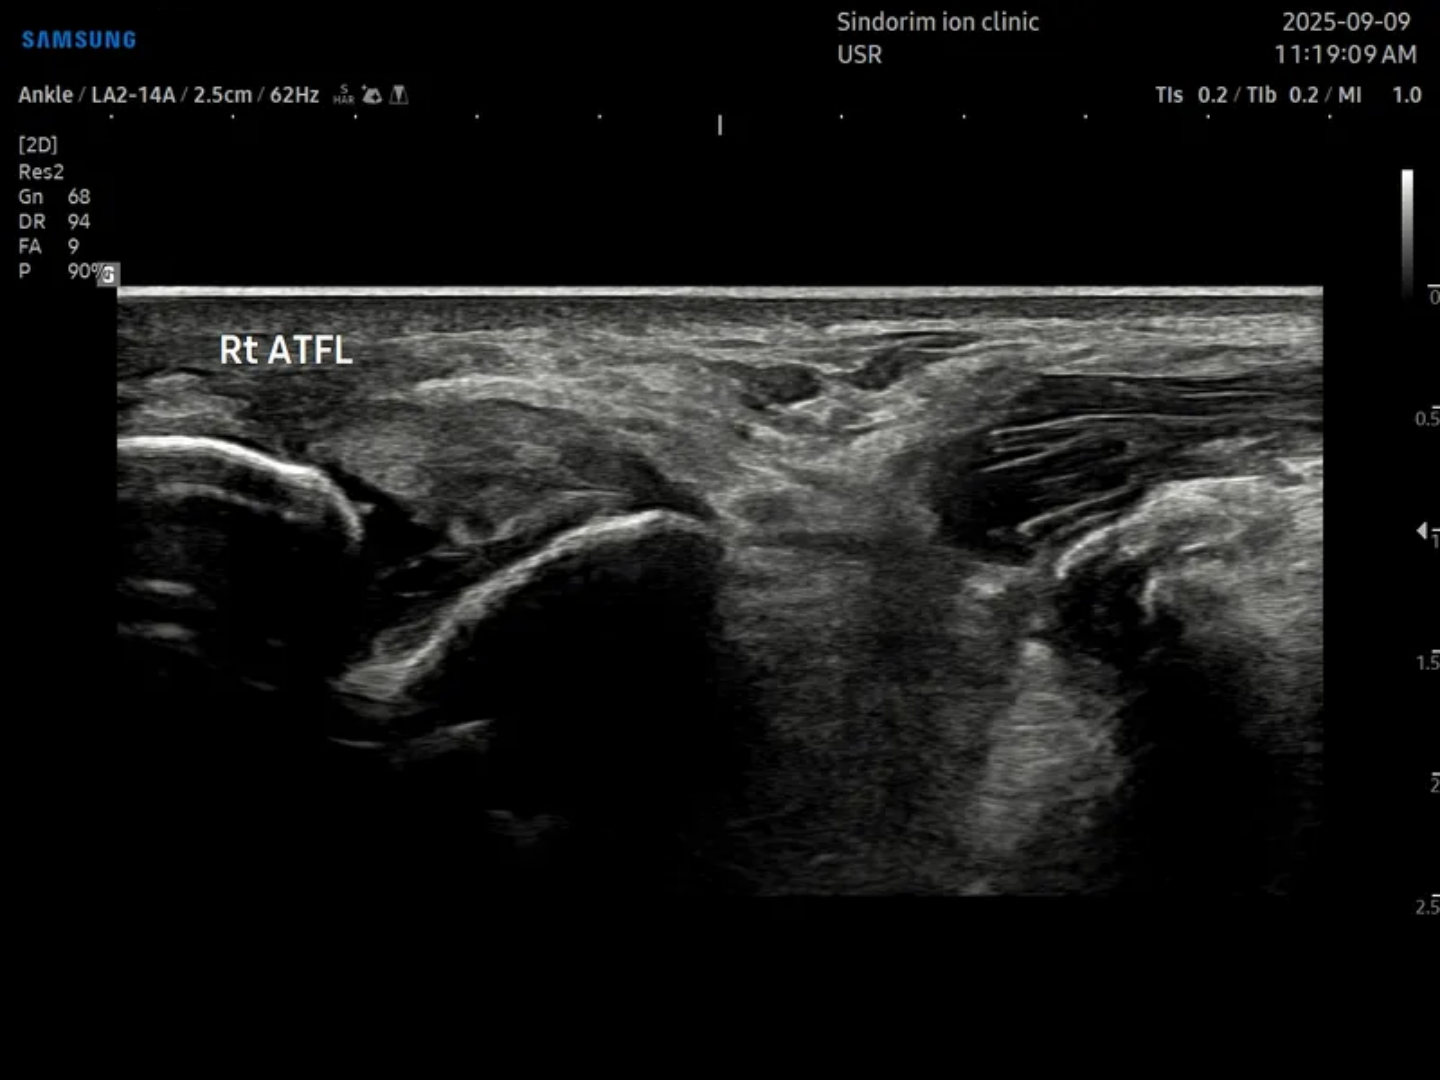

- 치료기간 : 25 . 4 . 19 ~ 25 . 9 . 0

- 치료횟수 : 20 회

치료 후 : 비골근 건은 10회차에 마무리 / ATFL은 20회차에 마무리